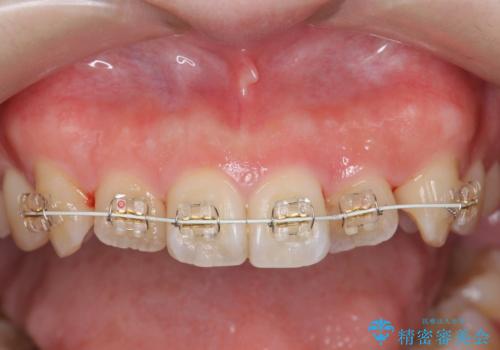

前歯のねじれを改善 小矯正+マウスピース矯正インビザライン

- 「前歯のねじれ、見た目を改善したい。」と矯正治療を希望され来院されました。

マウスピース矯正では改善の難しい前歯のねじれを前歯の部分ワイヤー矯正で改善したのち、インビザライン矯正を行い歯列を整えます。

インビザラインを行う前に前歯の部分矯正を行ったことで、しっかりとねじれが取れ整った歯列へと仕上げることが出来ました。